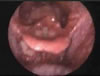

Ani kas kasılması.Bir kasın istek dışında olarak birden ve şiddetli olarak kasılması.